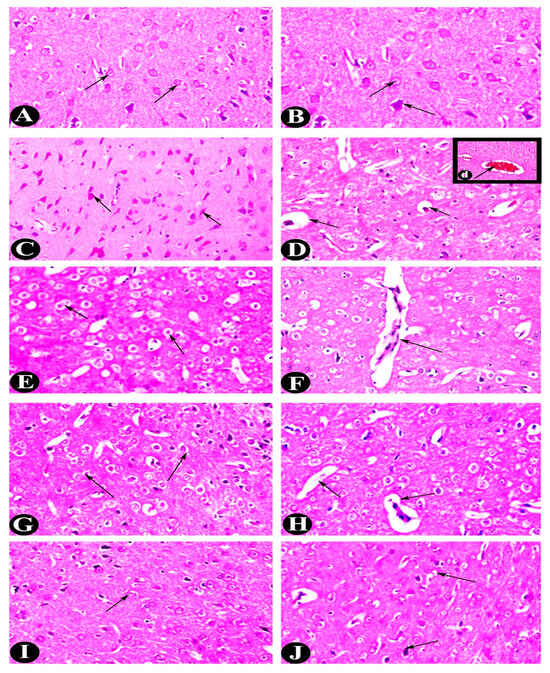

2.3. Histopathological Alterations (H&E)

| Groups | Average Cerebral Neurons (cells/mm2) | Degenerative Neurons (cells/mm2) | Average Glial (cells/m2) | Cerebellum Thickness (mm) | Number of Blood Vessels | Hippocampus Degenerative Neurons (cells/mm2) |

|---|---|---|---|---|---|---|

| Control | 25.500 ± 2.739 c | 10.313 ± 1.559 a | 42.333 ± 2.582 c | 48,948.180 ± 1997.897 c | 7.167 ± 1.722 c | 4.688 ± 0.552 a |

| EP | 13.333 ± 2.251 a | 19.254 ± 2.451 c | 29.500 ± 4.764 a | 38,617.459 ± 1783.434 a | 2.000 ± 1.095 a | 12.604 ± 1.074 b |

| EP-VPA | 20.333 ± 1.633 b | 14.844 ± 3.575 b | 40.167 ± 1.941 bc | 44,809.778 ± 1196.650 b | 3.333 ± 1.366 ab | 11.083 ± 1.139 b |

| EP-LO | 21.167 ± 2.137 b | 10.067 ± 0.467 a | 36.167 ± 2.229 b | 49,689.334 ± 2101.564 c | 4.500 ± 1.049 b | 6.417 ± 1.400 a |

| EP-LX | 22.167 ± 3.189 bc | 10.067 ± 0.467 a | 36.333 ± 2.805 b | 49,856.001 ± 3211.469 c | 5.000 ± 1.414 b | 6.417 ± 1.400 a |

| F value | 19.925 | 23.175 | 15.633 | 29.683 | 12.254 | 52.127 |

| p < | 0.0000 | 0.0000 | 0.0000 | 0.0000 | 0.0000 | 0.0000 |